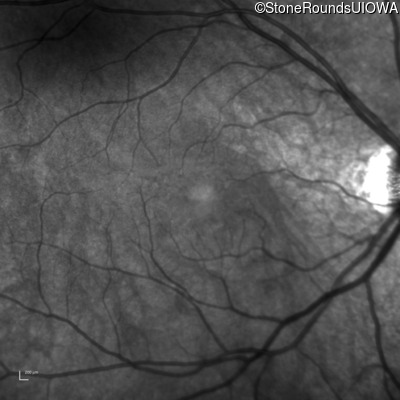

Infrared Fundus Photograph - Right - 20/40 +1

Exemplar